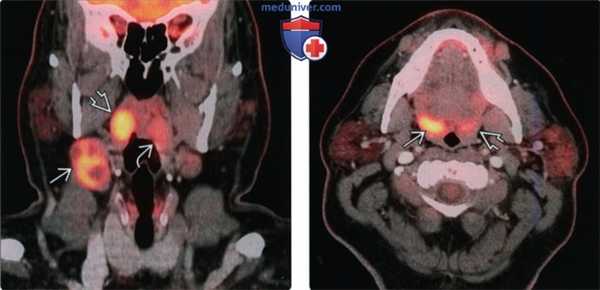

(Слева) При корональной ПЭТ/КТ у пациента с вновь возникшим пальпируемым образованием правой половины шеи определяется повышенное накопление ФДГ в крупном конгломерате лимфоузлов второго уровня, а также асимметричное накопление ФДГ в плоскоклеточном раке правой миндалины. Обратите внимание на отсутствие изменений со стороны левой миндалины.

(Справа) При аксиальной ПЭТ/КТ у этого же пациента определяется несимметрично повышенное накопление ФДГ в правой небной миндалине В по сравнению с противоположной стороной. При КТ с КУ не было обнаружено патологических изменений в этой области. Была выполнена биопсия, подтвердился ПКР.